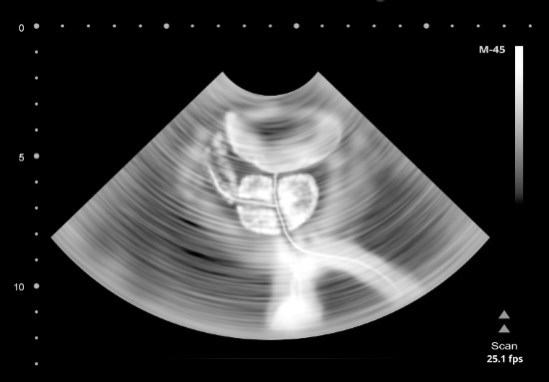

Иллюстрация к книге — Взламывая анатомию [image221.jpg]

Увеличенная простата может блокировать прохождение мочи в мочеиспускательном канале и усиливать позывы к мочеиспусканию.

Эта выводная трубка мочевыделительной системы выходит из самой низкой точки мочевого пузыря, что позволяет избежать застоя мочи. Длина мочеиспускательного канала у женщин составляет около 4 см. Он расположен между клитором и влагалищем и выполняет единственную функцию – выведение мочи. У мужчин же мочеиспускательный канал может быть длиной около 20 см. Он проходит через предстательную железу (простату), расположенную под мочевым пузырем, и выходит наружу в половом члене. К счастью, эякуляция и мочеиспускание не могут происходить одновременно. Поскольку простата и мочевая система мужчин тесно связаны, частое мочеиспускание или слабая струя мочи часто являются ранним признаком увеличения простаты. В более тяжелых случаях, когда отверстие мочеиспускательного канала полностью перекрывается, требуется срочное медицинское вмешательство, поскольку этот симптом может привести к различным патологиям мочевыводящих путей.